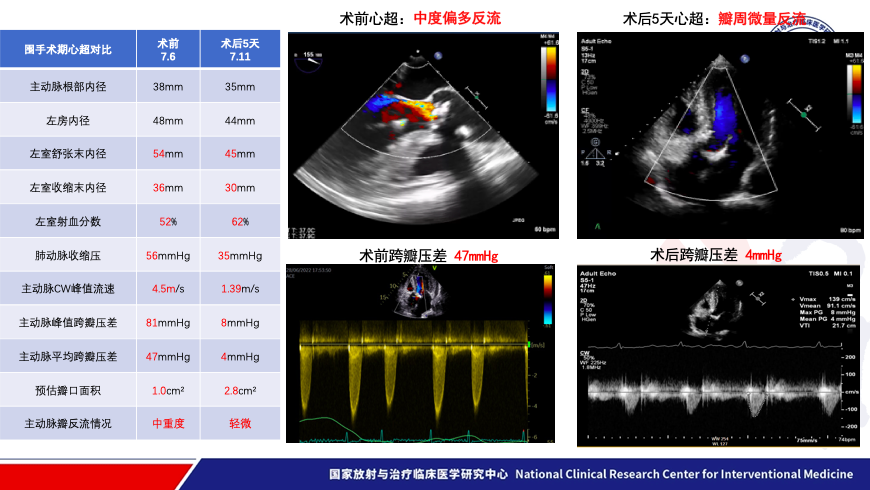

患者术后五天复查心超提示人工瓣架固定,开放不受限,峰值压差8mmHg,平均压差4mmHg.患者恢复良好,氨基末端利钠肽前体由术前5688pg/ml下降至1035pg/ml,NYHA心功能分级由III级改善至II级。术后一月复查时瓣膜工作状态良好,平均跨瓣压差 5mmHg。氨基末端利钠肽前体进一步下降至414pg/ml。